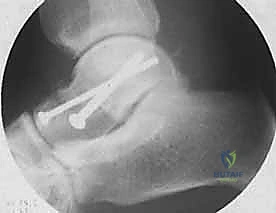

* مسامير التيتانيوم المجوفة (Cannulated Screws): مسامير قوية جداً يتم إدخالها عبر العظم لضغط أجزاء الكسر معاً.

* المسامير بدون رأس (Headless Compression Screws): تُستخدم في المناطق المغطاة بالغضروف، حيث تُدفن بالكامل داخل العظم لكي لا تحتك بالمفصل وتسبب تآكلاً.

* الشرائح المعدنية الدقيقة (Mini-Plates): تُستخدم أحياناً لتدعيم التثبيت في حالات التفتت الشديد (Comminution) حيث لا تكفي المسامير وحدها.

يتم وضع المسامير عادة من اتجاهين (من الأمام للخلف، ومن الخلف للأمام) لإنشاء هيكل ميكانيكي صلب يتحمل الضغوط.

المرحلة الخامسة: التحقق الإشعاعي الفوري والإغلاق

قبل إنهاء العملية، يستخدم الدكتور هطيف جهاز الأشعة السينية المتحرك داخل غرفة العمليات (C-arm Fluoroscopy) لأخذ صور متعددة والتأكد من:

1. المحاذاة المثالية للكسر.

2. عدم وجود أي فجوات أو درجات في السطح المفصلي.

3. الطول والموقع الصحيح للمسامير (للتأكد من أنها لا تخترق المفاصل المجاورة).